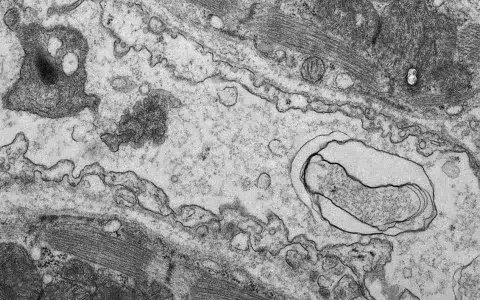

Doxorubicin treatment, which is commonly used in a variety of cancers, leads to cardiac atrophy and body wasting. Researchers from the Wihuri Research Institute and the University of Helsinki found that in mouse heart, doxorubicin leads to blood vessel rarefaction, which was prevented by treatment with gene therapy using the VEGF-B growth factor.

“Our findings show, that especially the endothelial cells, which form the inner surface of the vessels in the heart, have an essential role in the protection against the cardiotoxicity. More preclinical studies are needed though for the development of VEGF-B gene therapy for cardiac protection in patients”, elaborates Räsänen.